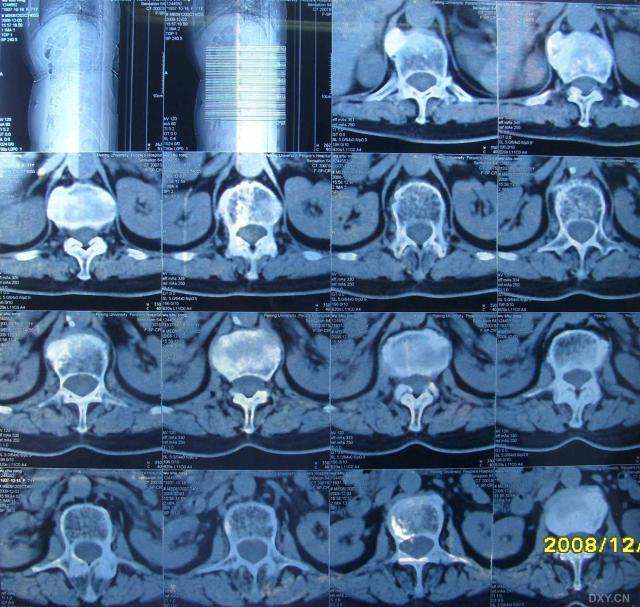

术前胸椎ct显示:t12右前外侧巨大骨质增生

患者,男性,31岁,外伤后腰背部疼痛,ct检查显示t12椎体骨折,l1椎体疑似